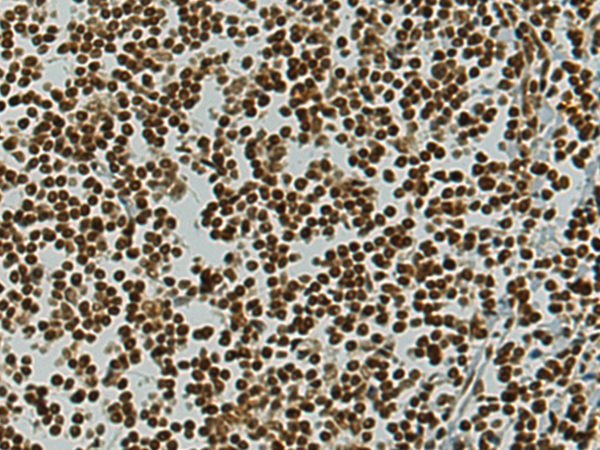

分类: 科研抗体货号: P02476别名: T3G; IMD17; CD3-GAMMA应用: WB反应种属: Human, Mouse